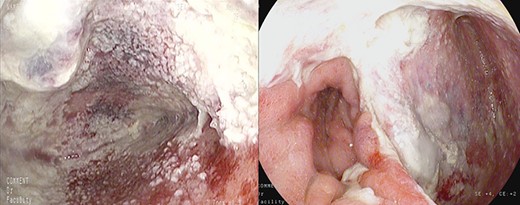

After the 14th session, the endoscopic evaluation showed a significantly cleaner and smaller cavity (1 cm). Two esophageal fully covered SEMS (Taewoong Niti-S Beta Stent) allowed the patient to have a liquid diet while the leak was safely healing: the stents were subsequently placed and kept for 3 weeks each. Endoscopy and esophagram were performed after SEMS removal, and they demonstrated leak resolution, with a tiny persistent depression at the site (Fig. 4). The patient has not had symptoms of recurrent fistula formation for over 6 months.